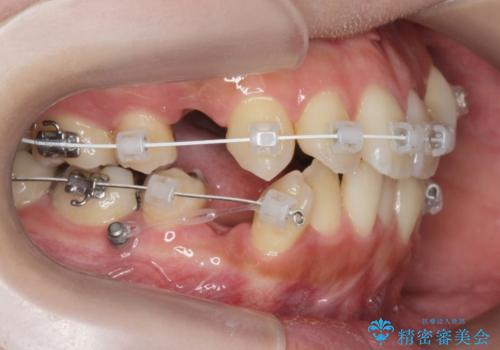

- ワイヤー矯正

- 八重歯・がたつきのある歯並びの改善を求めて来院されました。

全部の歯が入り切るスペースがなかったため、小臼歯4本を抜去しワイヤーを用いたマルチブラケット矯正を選択しました。

歯並びの改善と共に、歯ブラシがしやすくなった!と喜んでいただくことができました。